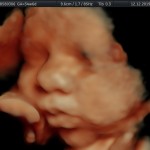

Los objetivos más importantes de esta ecografía son la evaluación de:

- Rastreo de alteraciones cromosómicas (sensibilidad del 55% aprox.).

- El escenario Gravídico: Placenta, liquido y Anexos.